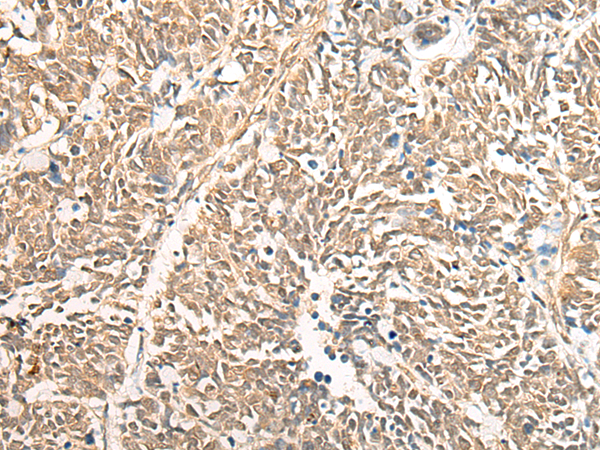

IHC positive control: |

Human brain;Human lung cancer |

IHC Recommend dilution: |

25-100 |